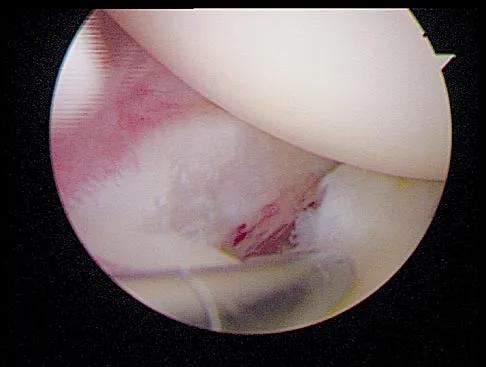

Question 73

A football player sustains a traumatic anterior inferior dislocation of the shoulder in the last game of the season. It is reduced 20 minutes later in the locker room. The patient is neurologically intact and has regained motion. If the patient undergoes arthroscopic evaluation, what finding is seen most consistently?

Explanation